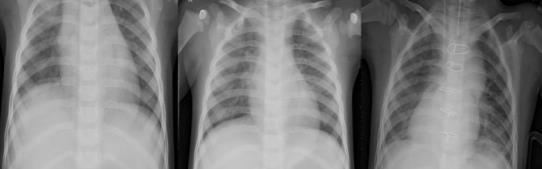

Thedatabaseisfurtherdividedintothreefolders(train, test,andval)withsubfoldersforeachimagecategory (Pneumonia/General).Figure1showsafewinstances of common and pneumonia photos that have been scaled to a static size. Due to the low amount of exposureinpatients,chestX-rayimagesalwaysshow symptomsoflimitedbrightness,andchestX-rayimages alwayshaveblack,white,andgreypants.

Thelungsareonbothsidesofthethoraciccavity,and the lung area is plainly visible on an X-ray since it is virtuallyblack.Theheart,whichissituatedbetweenthe lungs, appears practically as white as X-rays can go through it entirely. Because bones are comprised of proteinandareexceedinglydense,X-rayscannotpass through them, leaving the bones virtually white. Furthermore,theboneshavedistinctedges.

-1:Examplesfromthedataset.(a)normal cases, (b) pneumoniacases